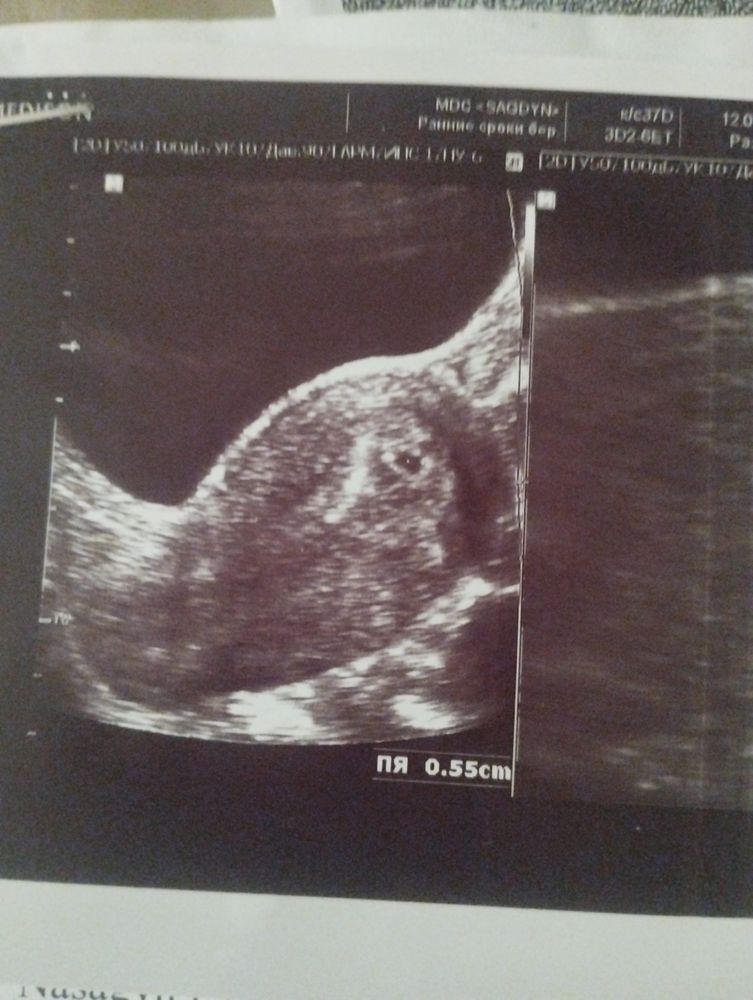

Плодное яйцо - это полость, где дальше будет развиваться малыш. Хорион - внешняя оболочка плодная яйца, из которой в будущем сформируется плацента, выполняет защитную и питательную функцию. Желточный мешок - временный «орган», который отвечает за кроветворение, обеспечивает также метаболические процессы. Совсем скоро рядом с ним появится эмбрион))

Вот на 3 том недели Изображение

Юля, видите черную точку это наш малыш и мне сердечко тогда помню послушать дали я заплакала

Елена , по менструации началась 7 неделя (6+2), Г сказала повторное через 2 недели, тогда должны увидеть сб

Нет признаков беременности в 4 нед.4 дня. 7 неделя, гематома 1.1×0.7